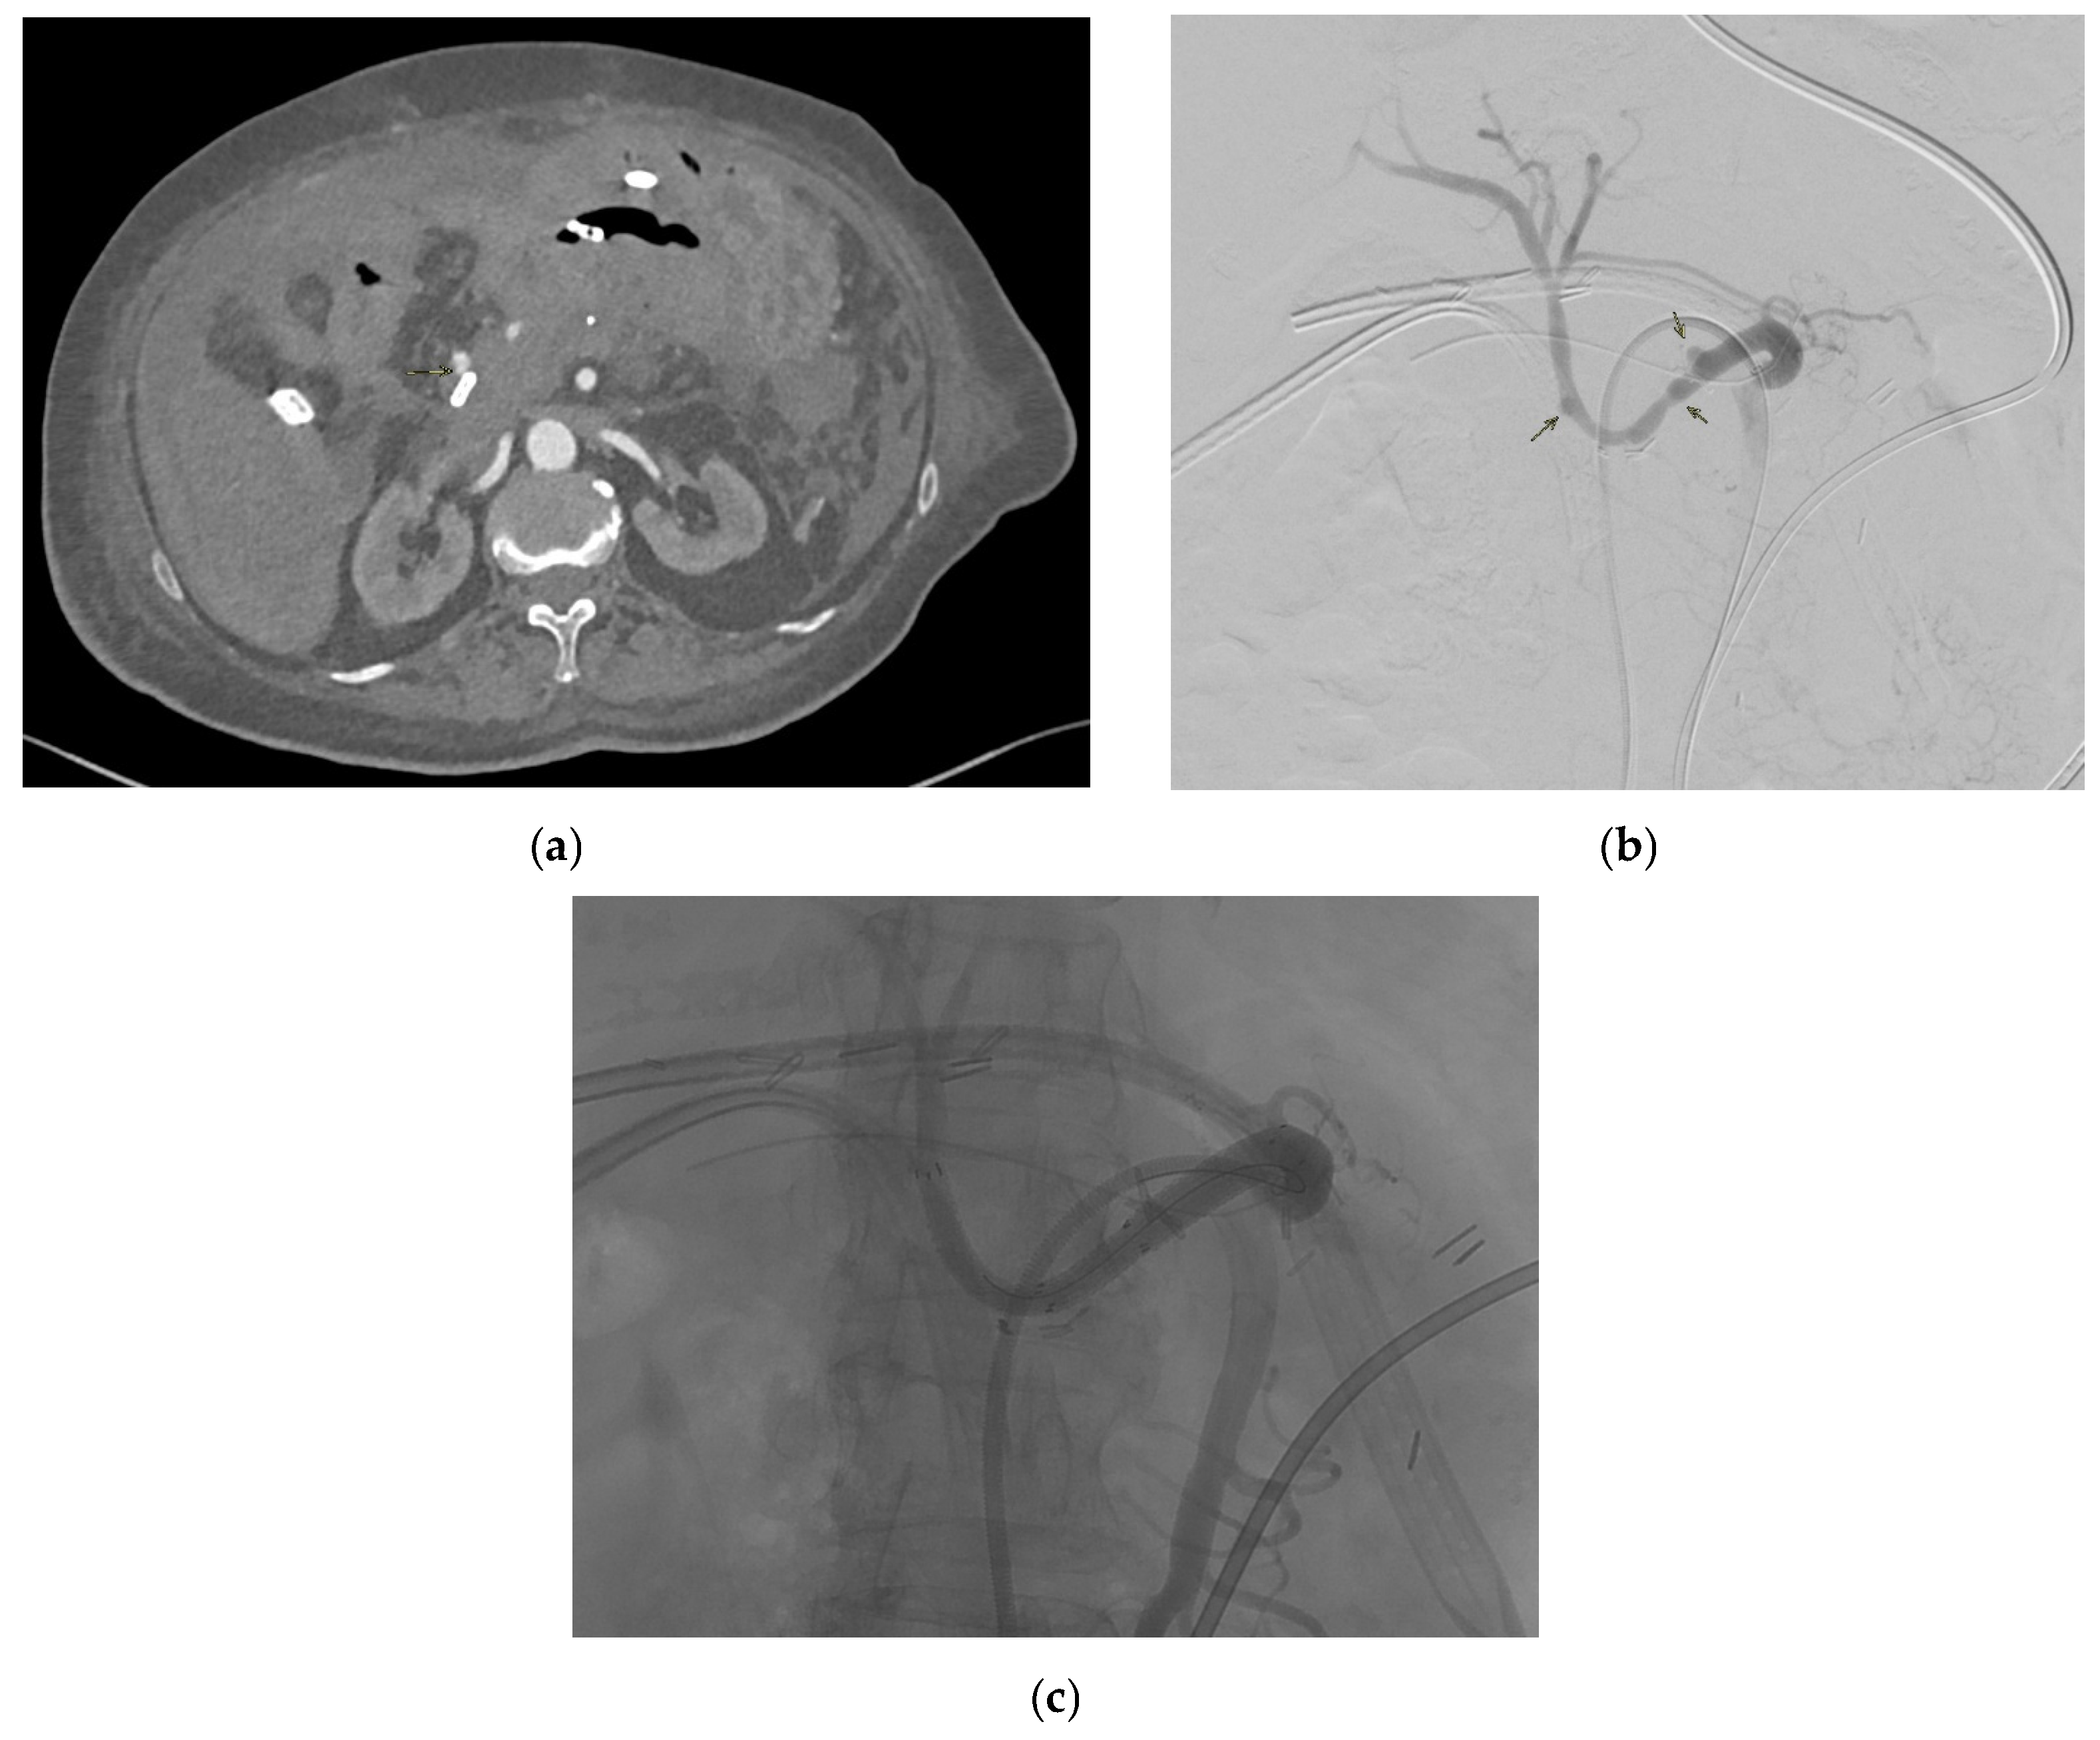

4.1. Inferior Mesenteric Artery

4.1.4. Diagnosis

4.1.5. Management